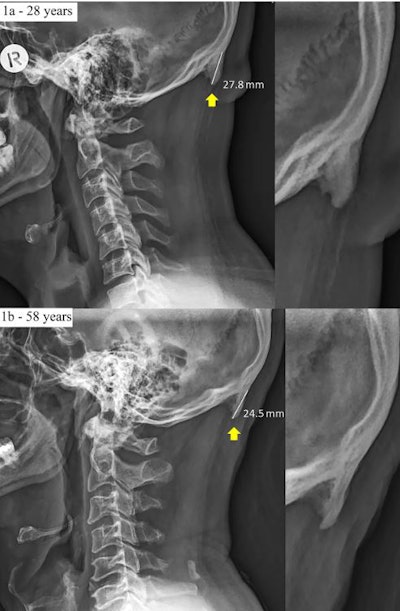

But the example that has been getting the most attention concerned the growth of "horns" in young adults who are heavy users of smartphones. The BBC article describes a paper published on 20 February 2018 in Nature's Scientific Reports in which Australian researchers discovered a higher prevalence of external occipital protuberances in the skulls of young adults -- bony outgrowths that they documented with radiography.

In their 2018 paper, David Shahar, PhD, and Mark Sayers, PhD, of the University of the Sunshine Coast examined the prevalence of enlarged external occipital protuberance (larger than 10 mm) in a population of 1,200 individuals ages 18 to 86. They found that male sex, younger age, and a higher degree of forward head protraction were positive links to the development of the protuberances.